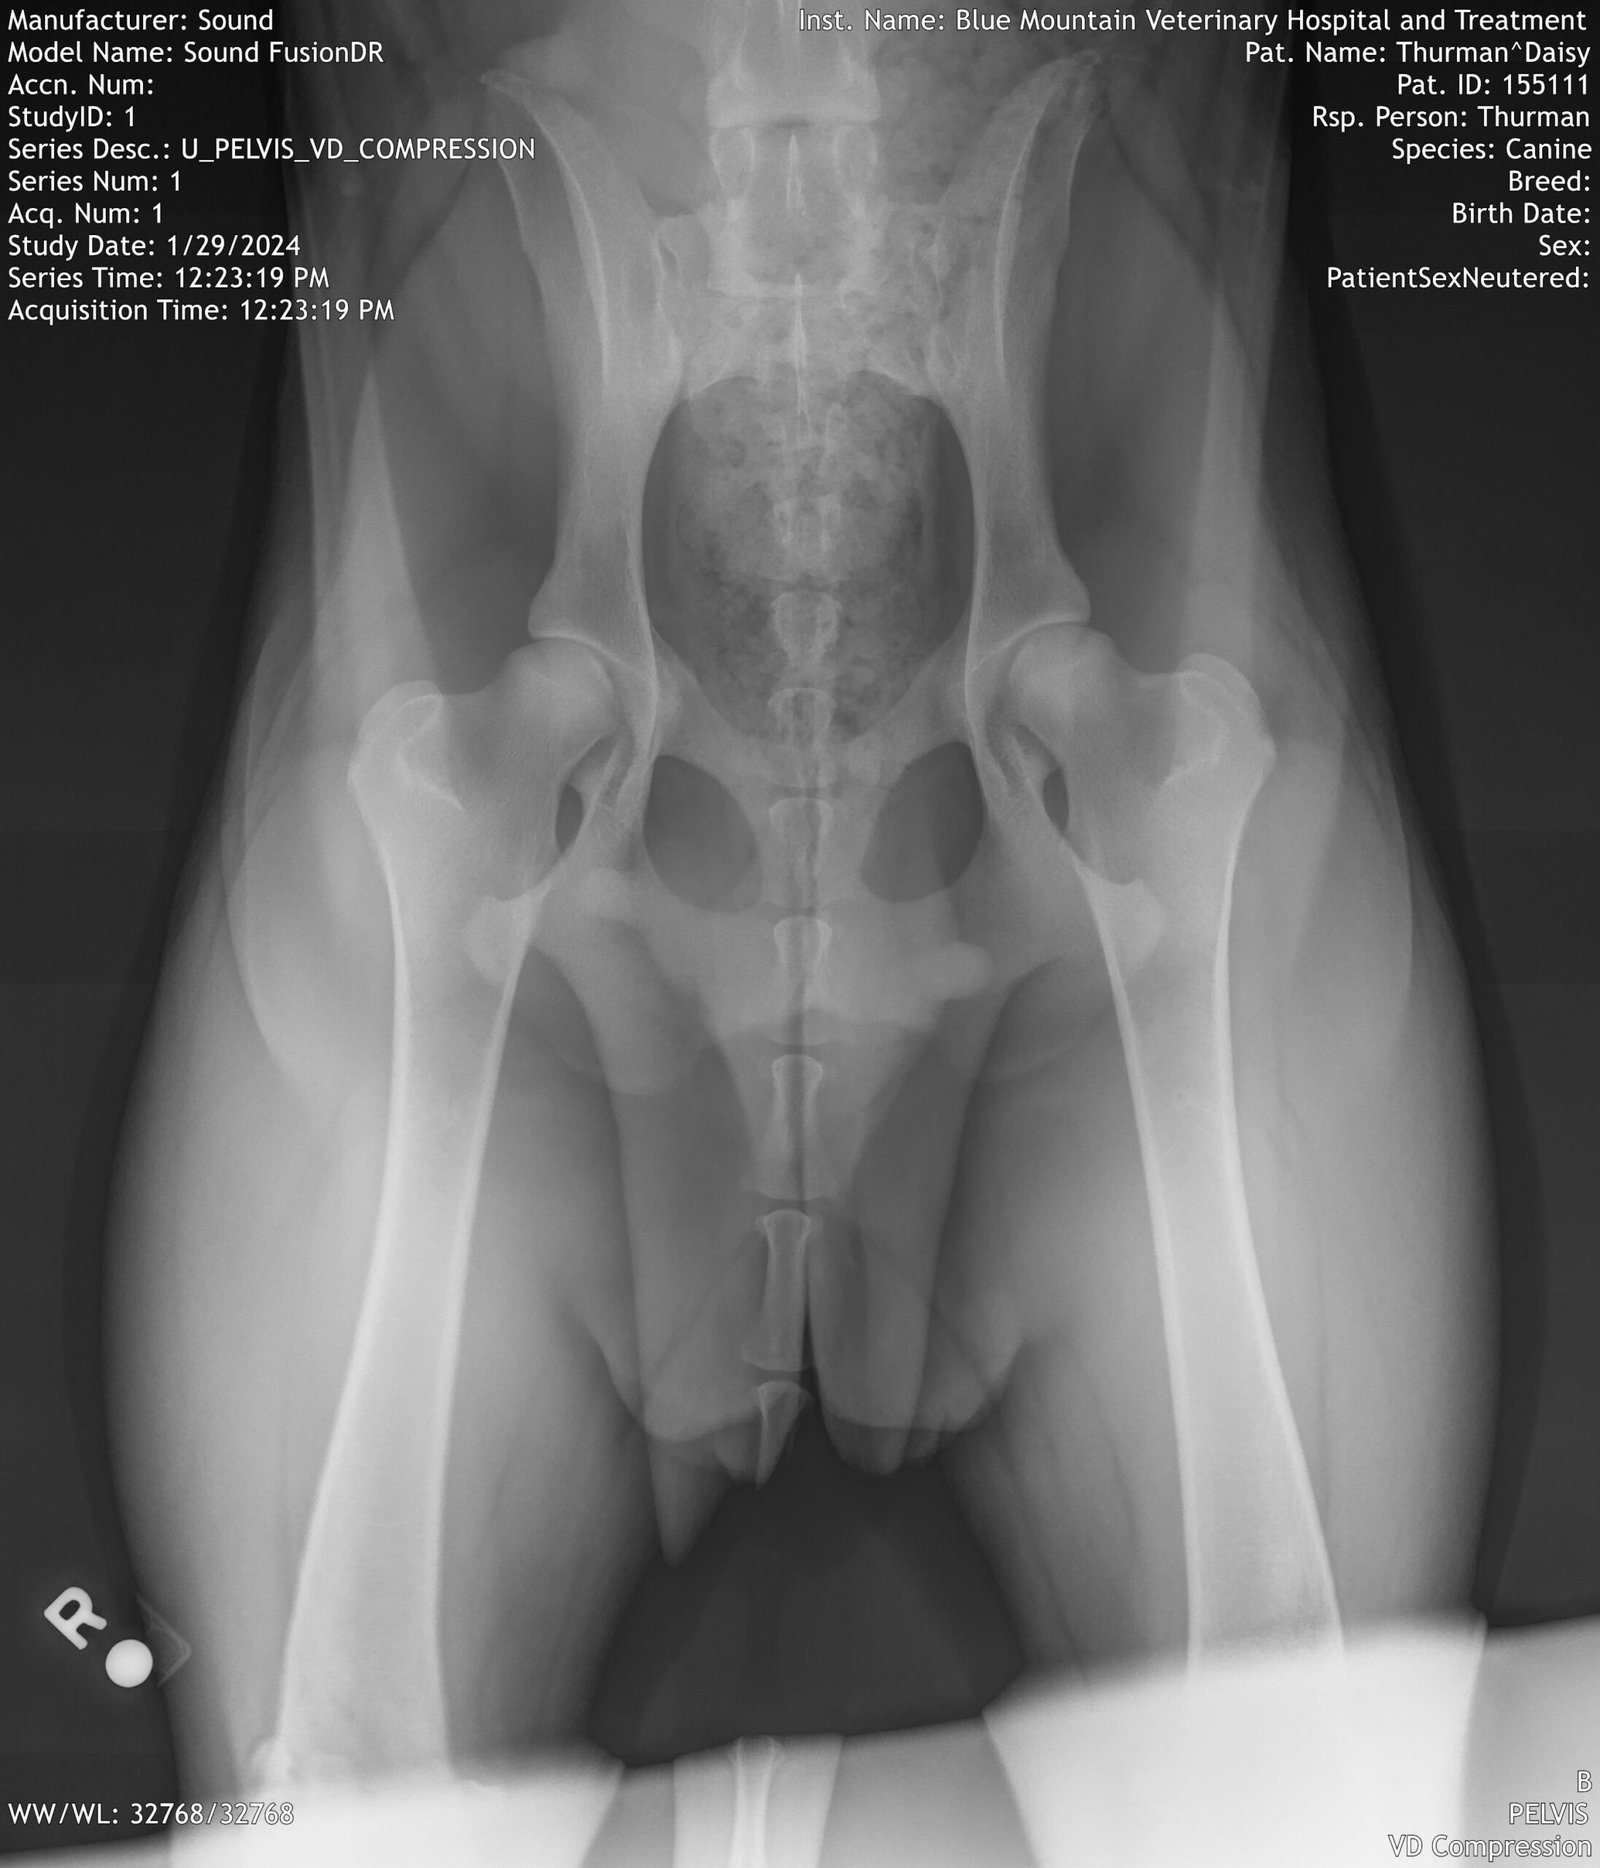

Apex Anatolians performs CHIC required minimum breed-specific health testing on every breeding dog! For the Anatolian Shepherd Dog, current CHIC required tests are HIPS and ELBOWS. Not one or the other- both.